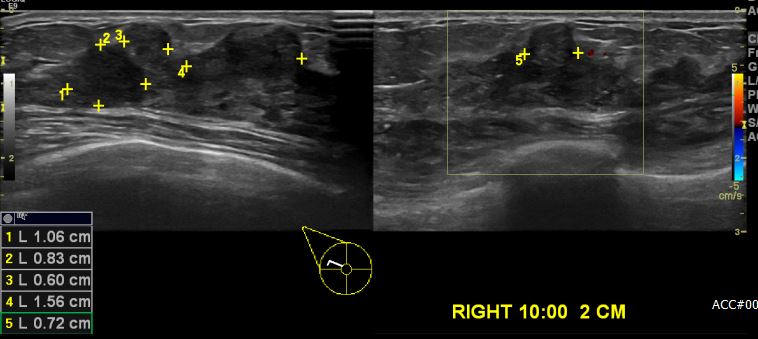

우측 유방통으로 내원하신 40대 여성 분으로 우측 유방 10시 방향에서 2cm 떨어진 거리의 의심스러운 혹 조직검사 시행하여 우측 침윤성 유관암 진단 되었습니다.